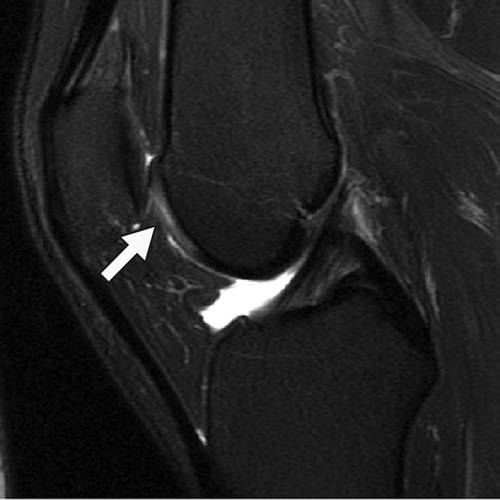

Incoming Term: 膝軟骨損傷, 膝軟骨損傷 手術 ブログ, 膝 軟骨 損傷 症状, 膝 軟骨損傷 サポーター, 膝 軟骨損傷 手術費用, 膝 軟骨損傷 原因, 膝 軟骨損傷 リハビリ, 膝 軟骨損傷 全治, 膝 軟骨損傷 mri, 膝 軟骨損傷 スポーツ復帰,